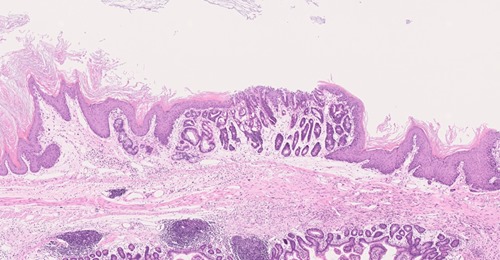

Dans une étude publiée dans le journal Cell Stem Cell, des chercheurs dirigés par Benjamin Beck, Chercheur qualifié FNRS et investigateur principal du #WELBIO à l’IRIBHM ULB - Université libre de Bruxelles, décrivent des mécanismes impliqués dans le changement des cellules de l’œsophage en cellules métaplasiques.

Des travaux auxquels a participé @Alizée Vercauteren Drubbel, financée par le Télévie. Alizée Vercauteren Drubbel et ses collègues ont combiné des outils de pointe en biologie moléculaire avec des modèles in vivo afin de disséquer les mécanismes régulant la transition d’un état cellulaire à un autre dans l’œsophage.